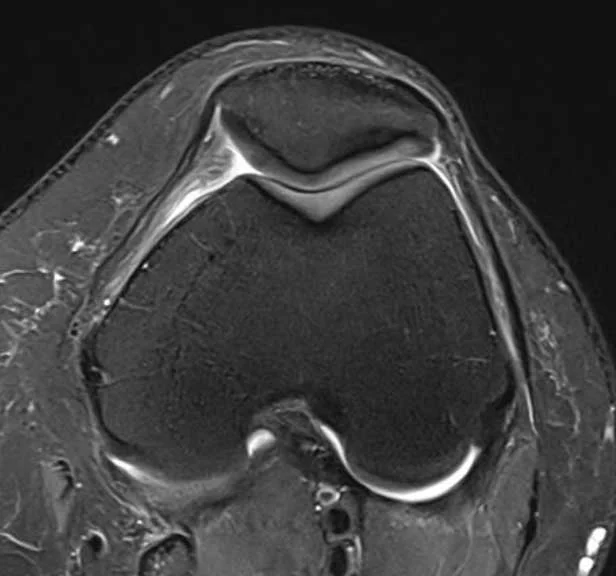

gesundes Knie

Für den gesunden Lauf der Kniescheibe in ihrer Gleitrinne sind vor allem wichtig:

- die Form der Kniescheibe

- die Form der Gleitrinne

- die Position des Ansatzes der Kniescheiben-Sehne („Tuberositas“)

- die Beinachse (X-Bein / O-Bein)

- die Drehung des Oberschenkelknochens